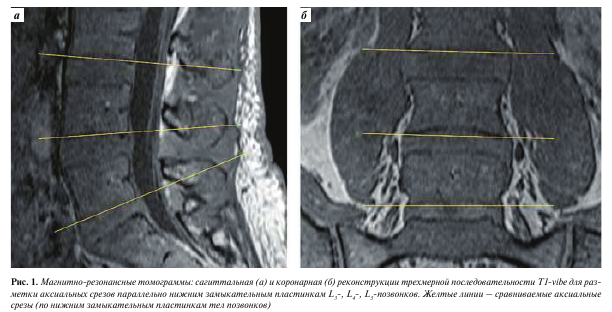

Изображения, полученные с помощью вышеописанной последовательности T1-vibe без жироподавления, открывали в программе InobitecPro в режиме мультипланарной реконструкции, где строились аксиальные срезы, параллельные в коронарной и сагиттальной проекциях нижним замыкательным пластинкам L3-, L4-, Ь5-позвонков (рис. 1). На построенных изображениях на всех 3 уровнях с помощью инструмента «ROI полигон» обводили многораздельные мышцы с обеих сторон, как показано на рис. 2 (вдоль границы остистого и суставного отростков, затем по фасции многораздельной мышцы), для оценки средней интенсивности сигнала и площади выделенной зоны. Кроме того, в режиме T1-vibe без жироподавления с помощью инструмента «ROI овал» измеряли среднюю интенсивность сигнала в жировой клетчатке слева от паравертебральных мышц (см. рис. 2).